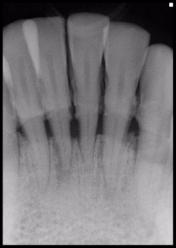

Radiographs